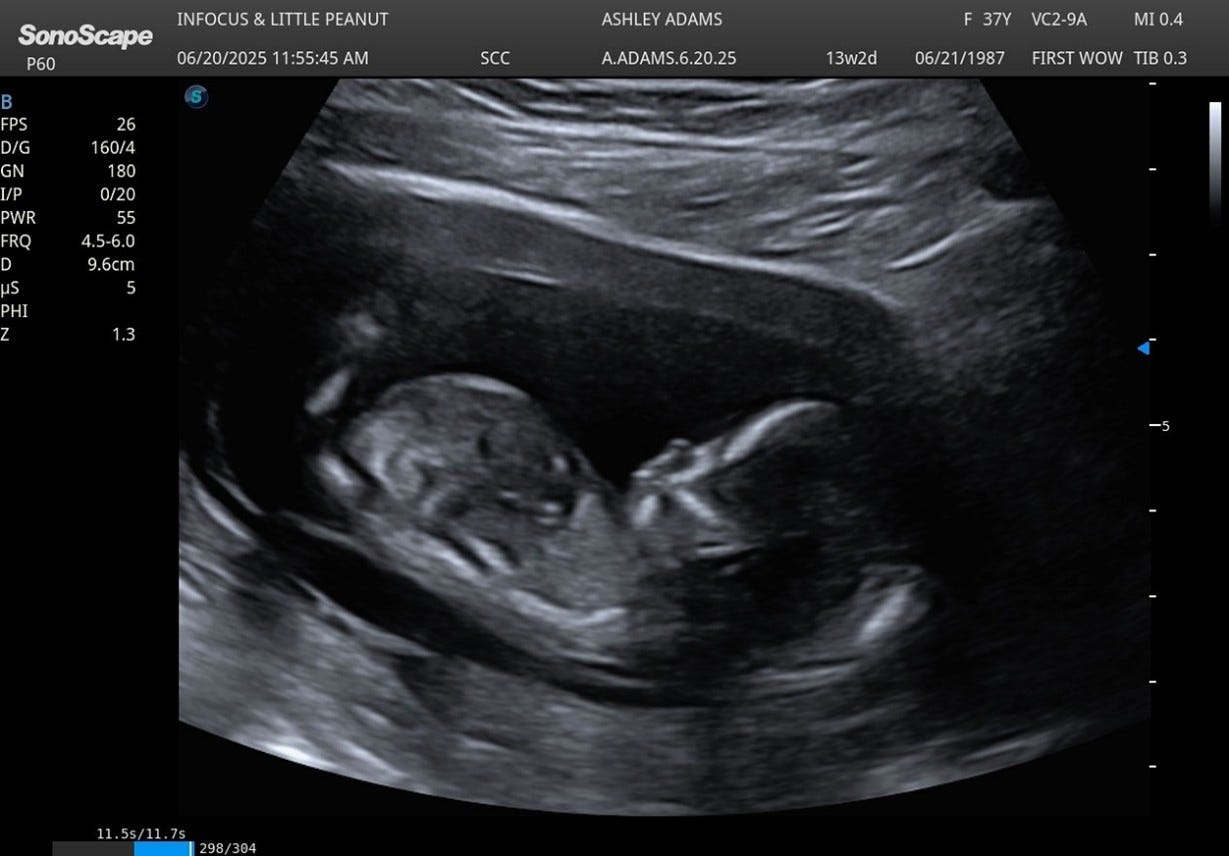

In April 2025, with that peace anchoring us, we implanted two more embryos, and this time, the embryos implantations stuck and the news came with joy, tempered by caution. We knew all too well the fragility of hope. We told no one at first, not because we lacked faith, but because we wanted to protect what was sacred and savor this moment we had waited 14 years to share.

For several weeks, everything looked strong. But around the 5 1/2-week mark, a series of stressful events, emotional strain, travel fatigue and a minor medical scare led to the loss of one of the embryos. A heartbeat that once flickered strong was suddenly gone. It was a moment of piercing grief, but also clarity. We allowed ourselves to mourn, but we did not spiral. This time, we knew how to anchor. The remaining embryo continued to grow, thriving against the odds and by week 6 1/2, the remaining baby’s heartbeat continued to be strong. Each doctor’s appointment came with cautious relief and more instructions for Ashley to take things easy. Our son began asking questions about the baby and although we agreed as a family not to share our good news just yet, he couldn’t wait to share the news with the sweet, older praying members of our church. The ones who pray with him, the ones he can hug when he is uneasy about something, the ones that correct him with a stern voice and tap on the rear. Sweet and all, but you know what all that means? News travelled quickly! Ashley’s ability to make an official announcement was almost completely taken because everyone was so excited for us! For Peyton, the shift was visible, tangible. He no longer saw the baby as a replacement, but as a gift to be shared. What was once uncertainty became anticipation and as summer pressed on, Ashley entered her second trimester. In August 2025, she is FIVE months pregnant with a healthy baby due in December. Nearly a year after our initial attempt, we are preparing for a new life.

By the time Ashley’s second trimester approached, we were no longer just waiting for a baby. We are preparing for a new chapter, one written not in desperation but in trust. One shaped not by what we thought we lost, but by what we know we gained. In December 2025, nearly a year from when the journey began, we will welcome another son; a boy born not just of science, but of prayer, patience and divine timing.